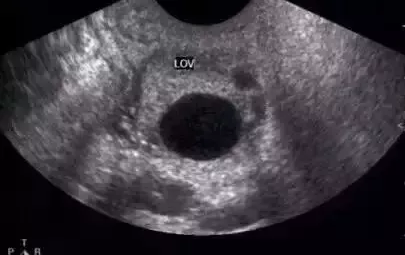

正常成熟的优势卵泡的声像图

① 卵泡最大直径达20mm,优势卵泡最大直径范围为17~24mm,体积2.5~8.5mm³。径小于17mm者为非成熟卵泡。

② 卵泡外形饱满呈圆形或椭圆形,内壁薄而清晰,或可见内壁卵丘所形成的一金字塔形的高回声,多在排卵前24~30小时易于显示。亦可见优势卵泡周围有一低回声晕(多由排卵前卵泡膜组织水肿所致)。

③ 卵泡位置移向卵巢表面,且一侧无卵巢组织覆盖,并向外突出。

卵泡的声像表现为圆形或椭圆形无回声区,位于卵巢皮质内,边界清晰,囊壁菲薄,内壁光滑。在月经的早期,卵巢皮质内可见多个直径3~5mm的小卵泡,随着月经周期的推移,卵泡逐渐增大,形成优势卵泡,而其它小卵泡逐渐萎缩。主导卵泡成熟,逐渐突出于卵巢表面。对卵泡的观察除注意其形态、数目、回声外,测量卵泡的大小对了解其生长发育状态、药物治疗效果以及判断卵泡成熟是十分重要的。